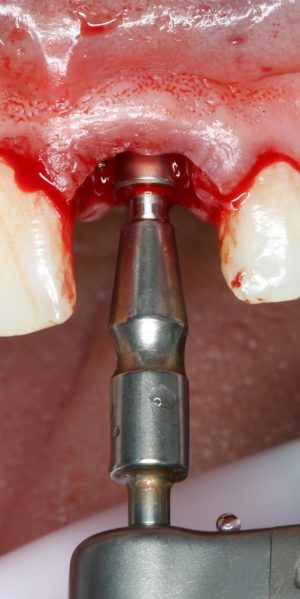

Прежде, чем приступить к аугментации (пластике) лунок зубов, мы подготовили лунки для имплантатов. В таких клинических случаях нет необходимости в использовании шаблона. Вместо этого, мы применяем общепринятые правила позиционирования и соблюдаем рекомендации производителя по хирургическому протоколу:

В процессе ирригации лунки промываются, что позволило нам еще раз подтвердить ранее сделанные выводы. С помощью аналогов имплантатов, входящих в хирургический набор Xive, мы проверили возможность стабилизации имплантатов в будущих лунках. Исходя из правил подбора и позиционирования имплантатов (я очень рекомендую почитать об этом здесь>>) мы остановились на Xive S диаметром 3,4 мм и длиной 13 мм.